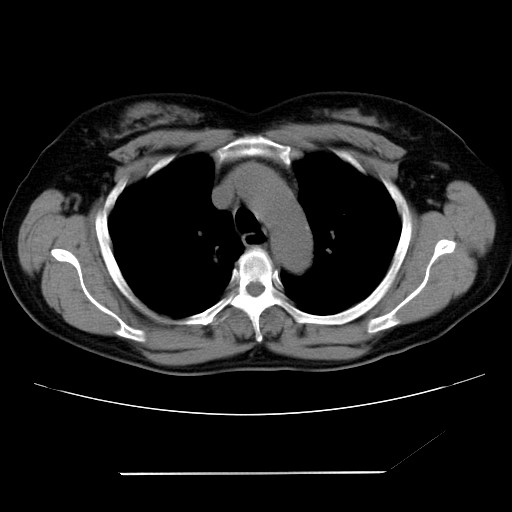

女性,62岁,长期咳嗽,既往从事工作有粉尘接触,有高血压病史,110/150mmhg,近日咳嗽加重,脸面浮肿,请大家帮看下,

1、尘肺;2、慢性支气管炎合并肺部感染;3、心影增大(左房、左室大),考虑高血压性心脏病。

慢支并肺部炎症;右肺结核球?主肺动脉、右肺动脉影不宽,右心室不大,不支持肺心病;无心包积液。